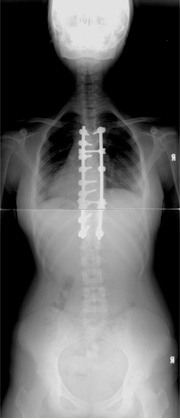

특발성 척추측만증 수술후